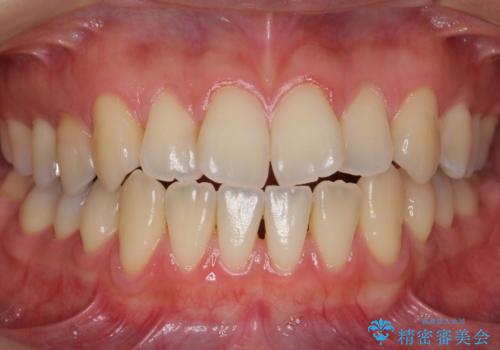

[ 前歯のねじれ・がたつき ] マウスピース矯正

![[ 前歯のねじれ・がたつき ] マウスピース矯正の症例 治療前](https://seimitsushinbi.jp/wp/wp-content/uploads/2024/02/4007c6479f6bce11863dcdd32ed5e39b-500x350.jpg?v=1708502552)

![[ 前歯のねじれ・がたつき ] マウスピース矯正の症例 治療後](https://seimitsushinbi.jp/wp/wp-content/uploads/2024/02/e7a01485e4f4dd0da04705fde4cc34cc-500x350.jpg?v=1708502585)